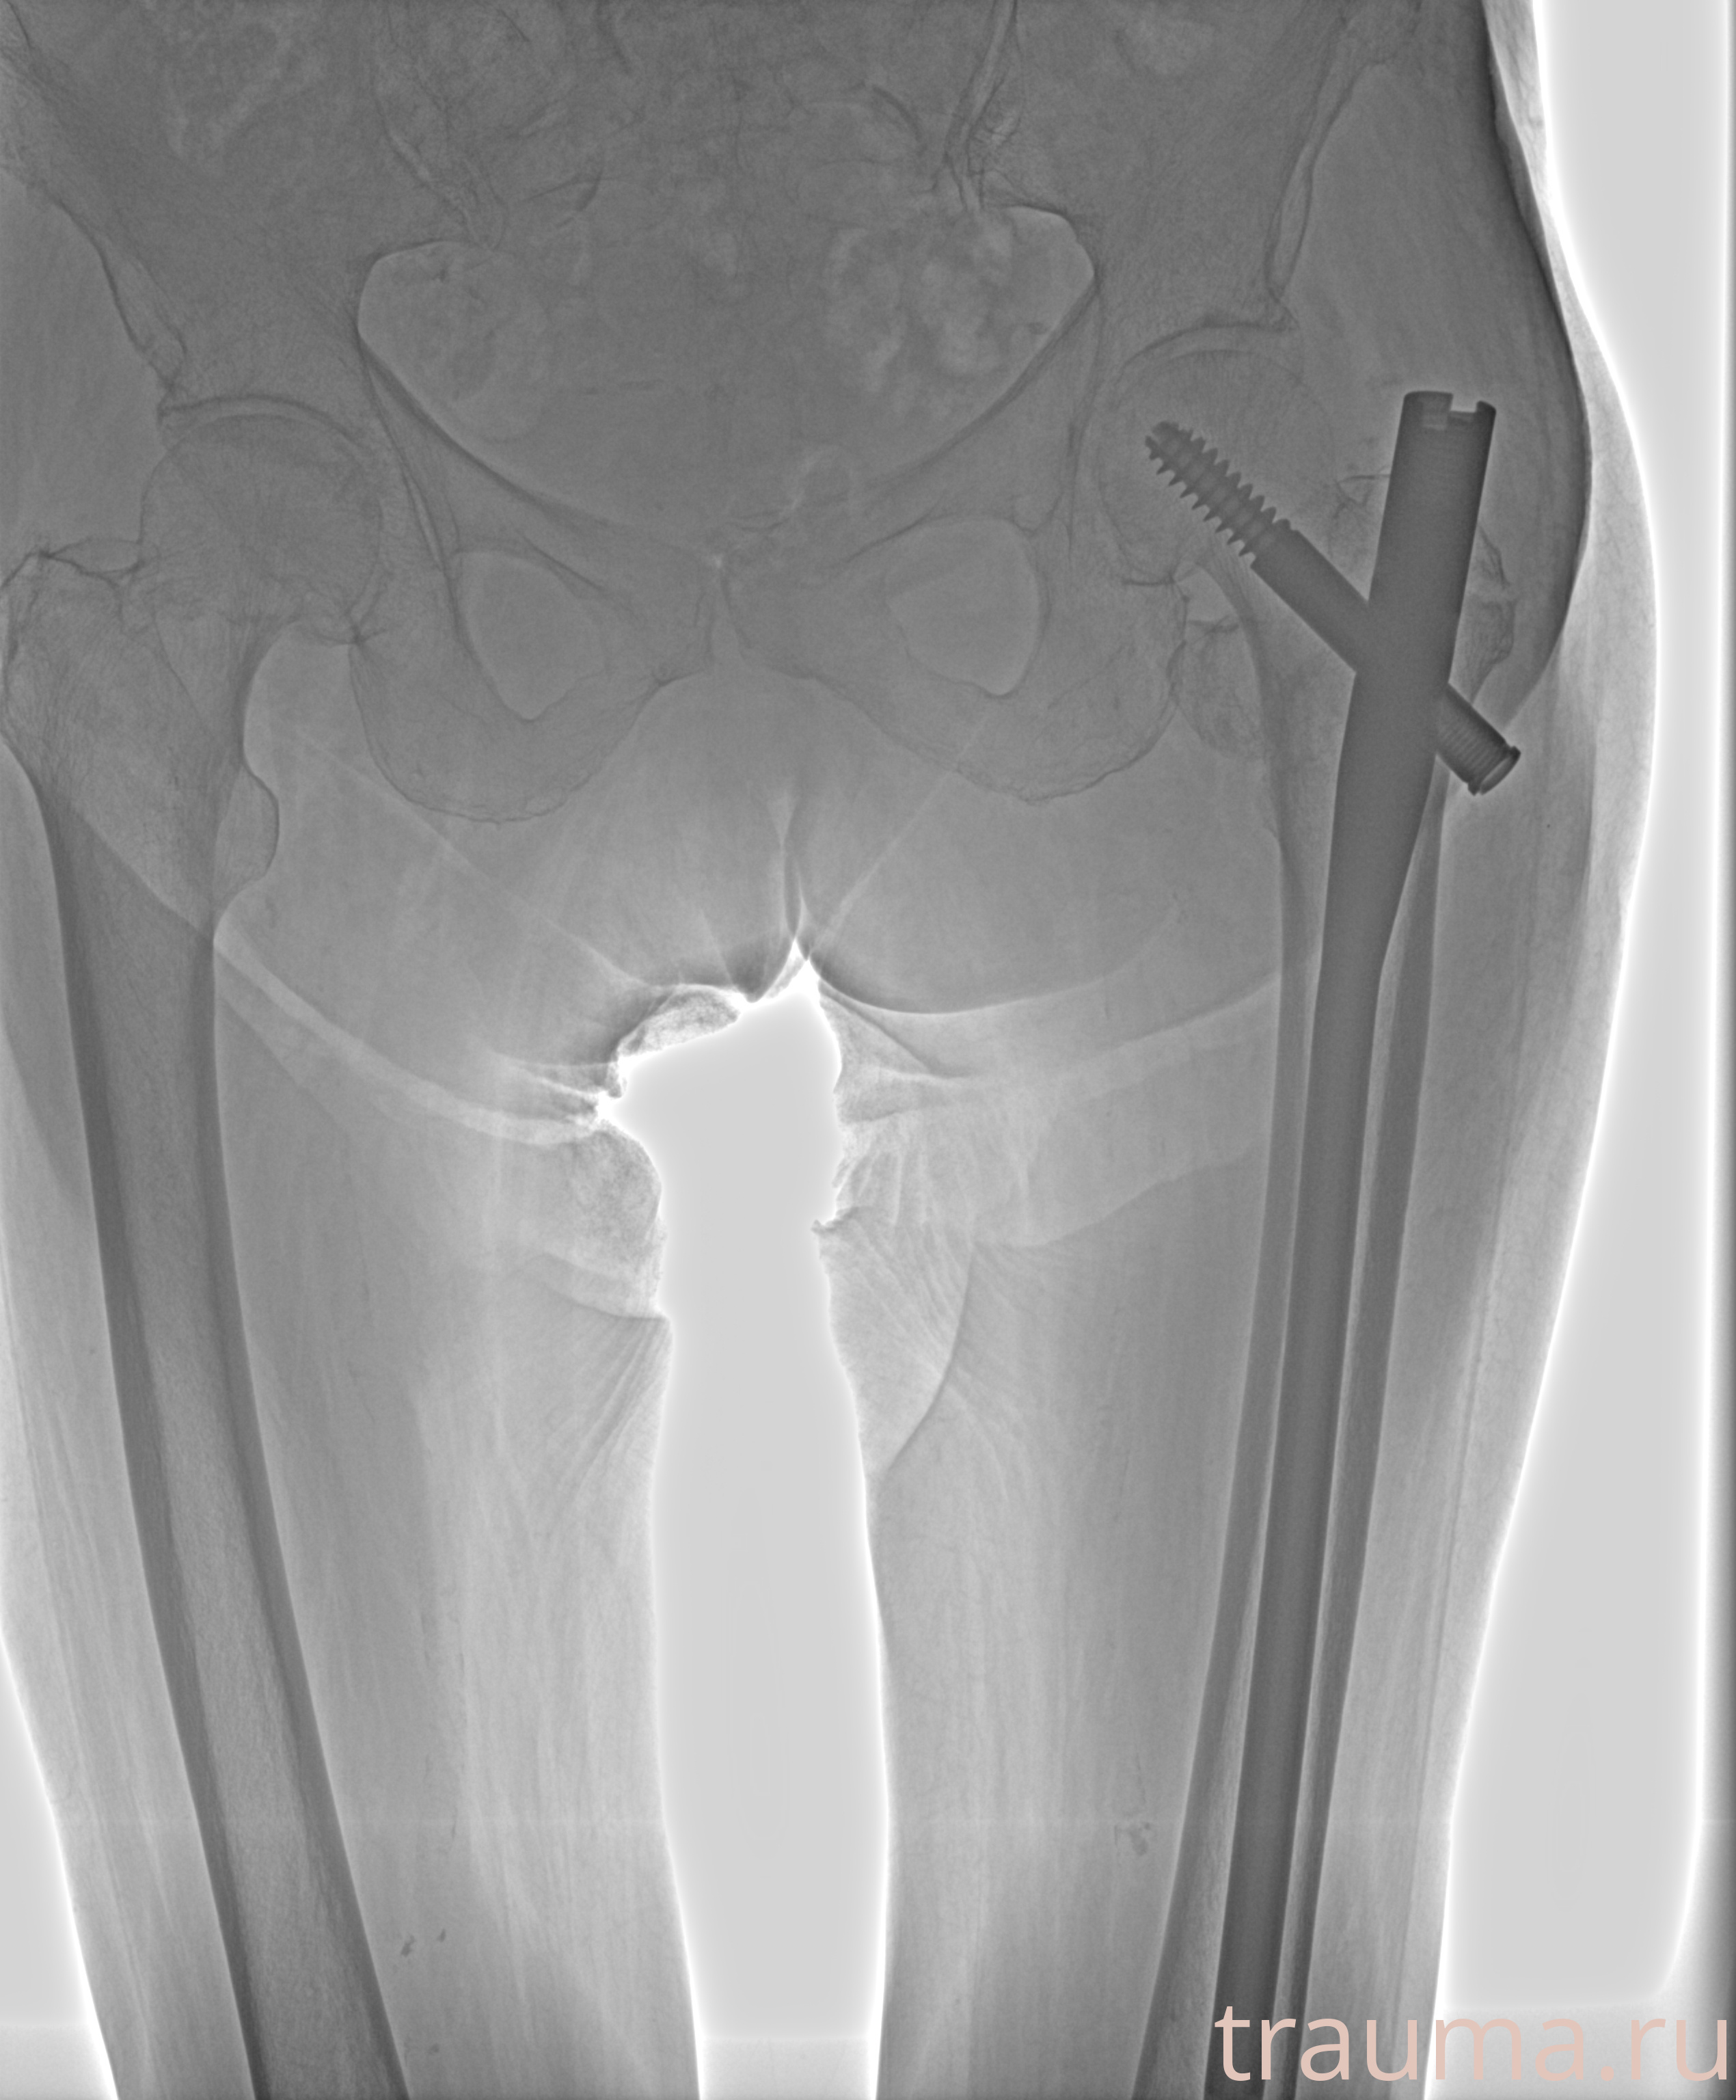

Рентгенограммы

Рентген на дому: по вашему адресу приезжает врач-рентгенолог, травматолог-ортопед с мобильным рентгеновским аппаратом, проводит диагностику травмы или заболевания, делает необходимые рентгенограммы, дает рекомендации по дальнейшему лечению. Получить качественные снимки в домашних условиях возможно благодаря уникальной методике, разработанной МосРентген Центром для института  Склифосовского